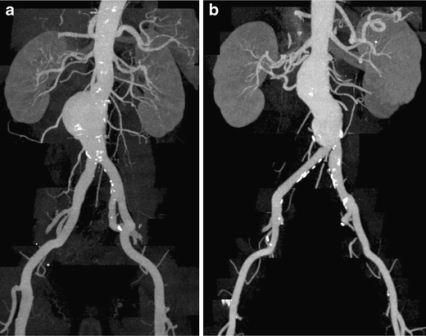

Angiografi merupakan pemeriksaan foto sinar-X untuk melihat pembuluh darah. Untuk mendapatkan gambaran pembuluh darah yang jelas pada foto sinar-X, maka sebelumnya perlu disuntikan zat kontras. Pada angiografi pembuluh darah perut, zat kontras bisa disuntikan melalui pembuluh darah besar di daerah lipat paha (arteri femoralis).

Fluoroskopi seringkali digunakan pada pemeriksaan angiografi pembuluh darah perut, dimana dihasilkan gambar pergerakan struktur di dalam tubuh, seperti "film" sinar-X. Pancaran sinar-X diberikan terus menerus pada bagian tubuh yang diperiksa, kemudian gambar yang dihasilkan dikirim ke monitor, sehingga bagian dalam tubuh dan pergerakannya bisa tampak dengan jelas.